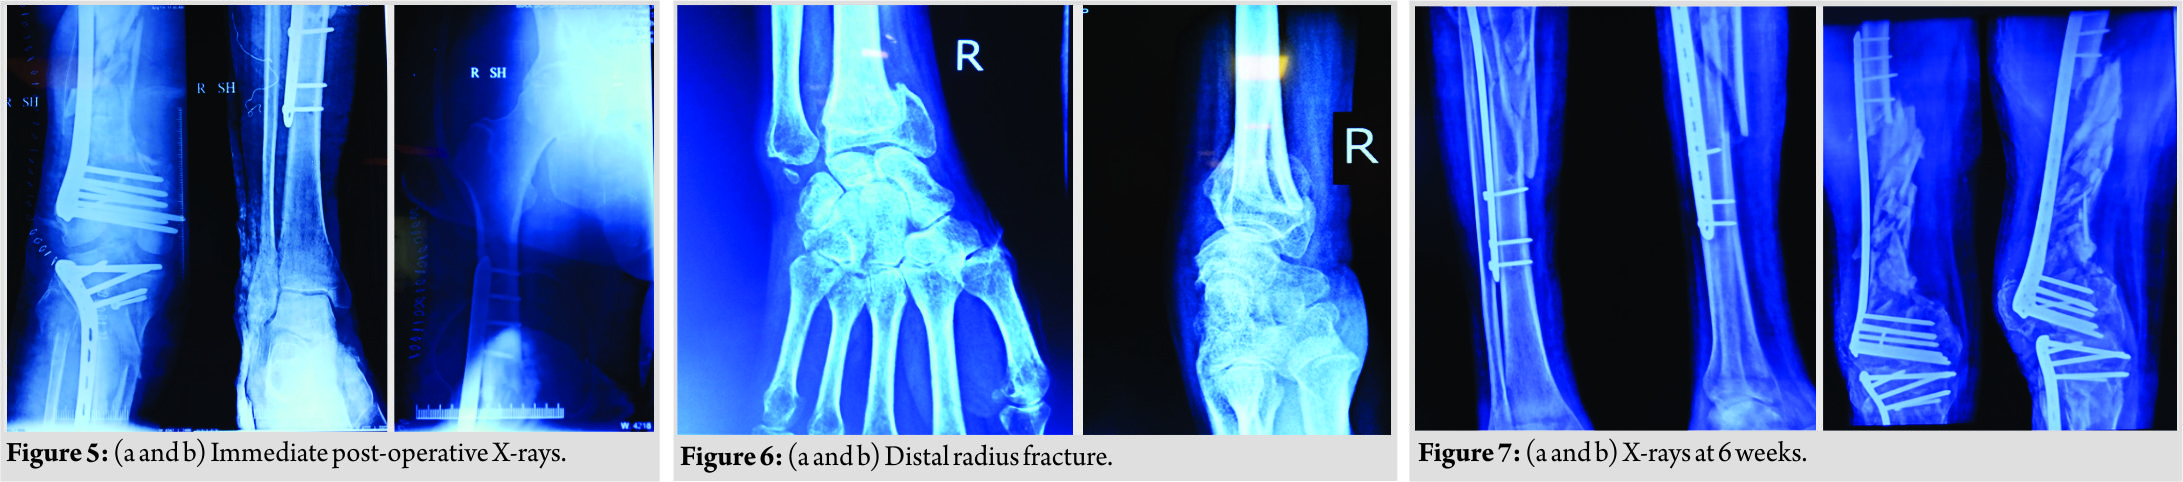

The patient was kept in the ICU till he was fit for subsequent intervention and appropriate treatment in the form of intravenous antibiotics and deep vein thrombosis prophylaxis was given. During this period, the patient had low-grade fever, but his inflammatory markers were normal and the wound over the thigh was healthy. On the 8th day, he was taken up in the operation theater with intubation on. Before removing external fixator, the wound present on anterior aspect of distal thigh was again debrided and found to be clean; then, the decision to proceed further was made and the external fixator was removed. The distal femur was opened through lateral approach using liberal skin incision (Fig. 4). After splitting the distal part of tensor fasciae latae, the distal locking screws were removed.Since the plate was bent, a bone hook was used to pull out the proximal end of plate laterally. Now, the position of the proximal screws was marked under C-arm control using an artery forceps. Each screw head was cleared causing minimal muscle damage and they were removed in a minimally invasive fashion, thus preserving the biology of zone of comminution and the plate was gently levered out. Following implant removal, we identified that there was another fracture line in coronal plane just posterior to plate application in the articular block which was identified as lateral condyle Hoffa fracture. The articular reconstruction was first done and the Hoffa fracture was fixed using single partially threaded cancellous screw. Manual linear traction was applied to the limb after reconstructing articular block and grossly comminuted fragments were seen to be aligned, so no attempt was made to open the comminuted area. The length of the limb was maintained by giving linear traction and an electrocautery was used to ensure that the center of femoral head, patella, and second toe lie in same line and checked under C-arm to maintain the correct rotation of the limb. The longest available distal femur locking plate (A.O SYNTHES) in the set was slid in a MIPPO fashion bypassing the zone of comminution after reconstructing the articular block. Same incision was extended below knee to expose proximal tibia and the longest available lateral tibia locking plate(A.O SYNTHES) was slid in a MIPPO manner bypassing the comminution. Now, after fixing both the fractures, the knee was examined for ligamentous instability and it was found to be globally unstable in both the planes. Considering the gross comminution in both femur and the tibia, and the being an open fracture, it was decided to wait for ligamentous reconstruction till bony union was achieved. Wound was sutured in layers over negative drain and a long knee brace was given to the patient since the knee was unstable in both the planes.The patient was shifted out of theater in an intubated state. Immediate post-operative X-rays revealed satisfactory alignment of both fractures, (Fig. 5). During the next 7 days, the patient remained intubated and during this period, the passive movement of joints was given, the limb was elevated and the stitch line was carefully monitored. Once the patient was extubated on the 8th day, it was found that there was an associated foot drop which was missed preoperatively since the patient was in an intubated state. The foot drop splint was applied accordingly and physiotherapy in the form of guarded ROM and muscle strengthening exercises was started. We could not ambulate the patient as he had another fracture in the wrist in the recent past, (Fig. 6).

After splitting the distal part of tensor fasciae latae, the distal locking screws were removed.Since the plate was bent, a bone hook was used to pull out the proximal end of plate laterally. Now, the position of the proximal screws was marked under C-arm control using an artery forceps. Each screw head was cleared causing minimal muscle damage and they were removed in a minimally invasive fashion, thus preserving the biology of zone of comminution and the plate was gently levered out. Following implant removal, we identified that there was another fracture line in coronal plane just posterior to plate application in the articular block which was identified as lateral condyle Hoffa fracture. The articular reconstruction was first done and the Hoffa fracture was fixed using single partially threaded cancellous screw. Manual linear traction was applied to the limb after reconstructing articular block and grossly comminuted fragments were seen to be aligned, so no attempt was made to open the comminuted area. The length of the limb was maintained by giving linear traction and an electrocautery was used to ensure that the center of femoral head, patella, and second toe lie in same line and checked under C-arm to maintain the correct rotation of the limb. The longest available distal femur locking plate (A.O SYNTHES) in the set was slid in a MIPPO fashion bypassing the zone of comminution after reconstructing the articular block. Same incision was extended below knee to expose proximal tibia and the longest available lateral tibia locking plate(A.O SYNTHES) was slid in a MIPPO manner bypassing the comminution. Now, after fixing both the fractures, the knee was examined for ligamentous instability and it was found to be globally unstable in both the planes. Considering the gross comminution in both femur and the tibia, and the being an open fracture, it was decided to wait for ligamentous reconstruction till bony union was achieved. Wound was sutured in layers over negative drain and a long knee brace was given to the patient since the knee was unstable in both the planes.The patient was shifted out of theater in an intubated state. Immediate post-operative X-rays revealed satisfactory alignment of both fractures, (Fig. 5). During the next 7 days, the patient remained intubated and during this period, the passive movement of joints was given, the limb was elevated and the stitch line was carefully monitored. Once the patient was extubated on the 8th day, it was found that there was an associated foot drop which was missed preoperatively since the patient was in an intubated state. The foot drop splint was applied accordingly and physiotherapy in the form of guarded ROM and muscle strengthening exercises was started. We could not ambulate the patient as he had another fracture in the wrist in the recent past, (Fig. 6). The wound healing was bit delayed but it was ultimately uneventful. An X-ray was taken at 6 weeks post-operative which revealed satisfactory alignment (Fig. 7) and toe touch weight-bearing with long knee brace was started under supervision of trained physiotherapists. The patient was further followed up at 1 month interval and during this rehabilitation period, special attention was given to his psychiatric care. At the latest follow-up of 6 months, the patient had radiological and clinical evidence of union (Fig. 8). At the last available follow-up,the ligamentous instability still persisted, and with long knee brace, he was able to stand and walk. The foot drop was also recovering and there was no extension lag and knee flexion was upto 90° (Fig. 9). At this moment, he was properly counseled and explained in detail about all the available options in the form of arthrodesis, hinged knee arthroplasty, and ligamentous reconstruction, but the patient opted for non-operative management in the form of long knee brace for the time being.

The wound healing was bit delayed but it was ultimately uneventful. An X-ray was taken at 6 weeks post-operative which revealed satisfactory alignment (Fig. 7) and toe touch weight-bearing with long knee brace was started under supervision of trained physiotherapists. The patient was further followed up at 1 month interval and during this rehabilitation period, special attention was given to his psychiatric care. At the latest follow-up of 6 months, the patient had radiological and clinical evidence of union (Fig. 8). At the last available follow-up,the ligamentous instability still persisted, and with long knee brace, he was able to stand and walk. The foot drop was also recovering and there was no extension lag and knee flexion was upto 90° (Fig. 9). At this moment, he was properly counseled and explained in detail about all the available options in the form of arthrodesis, hinged knee arthroplasty, and ligamentous reconstruction, but the patient opted for non-operative management in the form of long knee brace for the time being.